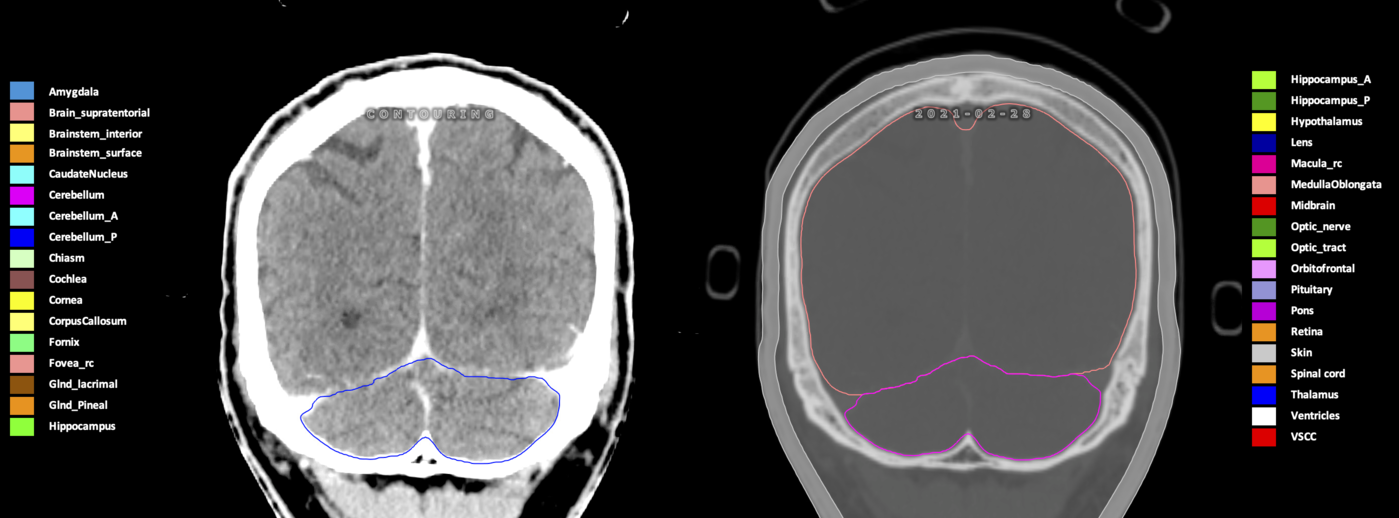

Eekers et al. have published an international neurological atlas for contouring of organs at risk in consensus with the European Particle Therapy Network (EPTN) in 2018 and an update in 2021. The purpose of this consensus atlas is to decrease inter- and intra-observer variability in delineating OARs relevant for neuro-oncology.

Included are all OARs known to be relevant for radiation-induced toxicity in neuro-oncology: brain, brainstem (midbrain, pons, medulla oblongata), chiasm, cerebellum (anterior & posterior), cochlea, cornea, hippocampus (anterior & posterior), hypothalamus, lens, lacrimal gland, optic nerve, pituitary, skin, and vestibular & semicircular canals. To further facilitate research on cognition, vision and radiological changes after irradiation of the brain, potential clinically-relevant OARs are included: amygdala, caudate nucleus, cerebellum (anterior & posterior), corpus callosum, fornix, macula, optic tract, orbitofrontal cortex, periventricular space (PVS), pineal gland, and thalamus.

Three-dimensional delineation of the 25 consensus OARs for neuro-oncology are shown on CT (WW/WL 120/40, 3000/600), 3T MR images, (T1Gd, T2FLAIR 1mm) and 7T MR (MP2RAGE 0.7 mm). All are presented in transversal, sagittal and coronal view.